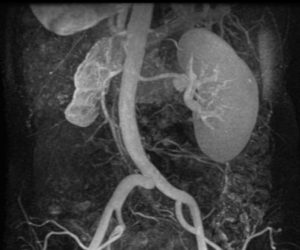

Для определения патологии используются различные диагностические процедуры:

- МРТ;

- Урографическое исследование – рентген почечных структур с применением контраста;

- Нефросцинтиграфия исследование органа с использованием радиоактивных материалов;

- Радиоизотопная диагностика – радиоактивный состав вводится внутривенно;

- Уретеропиелография – контрастное вещество вводят путем катетеризации в мочеточник;

- Ангиографическая диагностика – когда в крупные сосуды вводят контрастное вещество.